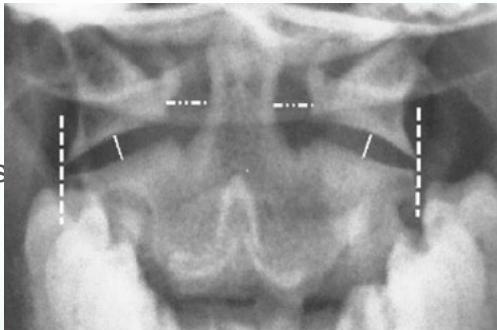

Open-Mouth View

- For C1 and C2

- Odontoid fractures

- Lateral mass fractures

- Look for:

- Symmetry

- Continuity of bone